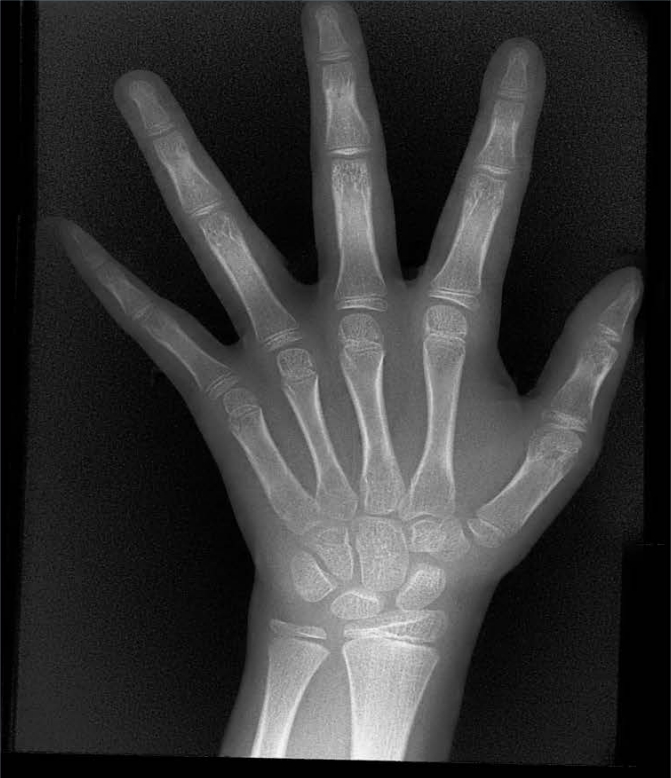

X射線骨齡儀通過拍攝兒童手腕部(指骨、掌骨、腕骨)的X射線影像,依據(jù)骨骼的形態(tài)、大小、鈣化程度等特征,結(jié)合評估標準(如《中國青少年兒童手腕骨成熟度及評價方法》,簡稱《中華-05》標準)進行骨齡判定。相較于傳統(tǒng)檢測方式,X射線骨齡儀具有輻射劑量低、影像清晰度高、檢測效率高的優(yōu)勢,能精準捕捉骨骼發(fā)育的細微變化,為骨齡評估的準確性提供保障。